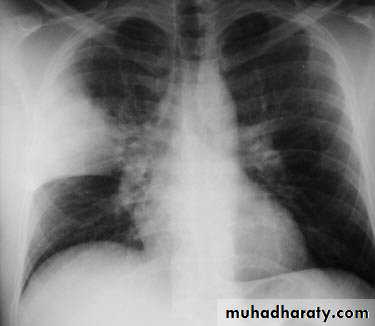

Chest X-ray shows mottled opacities in both lung fields, chiefly in the lower zones (Bronchopneumonia).

• Bronchopneumonia: Typically patchy and segmental shadowing

Bronchopneumonia: refers to more patchy alveolar consolidation associated with bronchial and bronchiolar inflammation often affecting both lower lobes